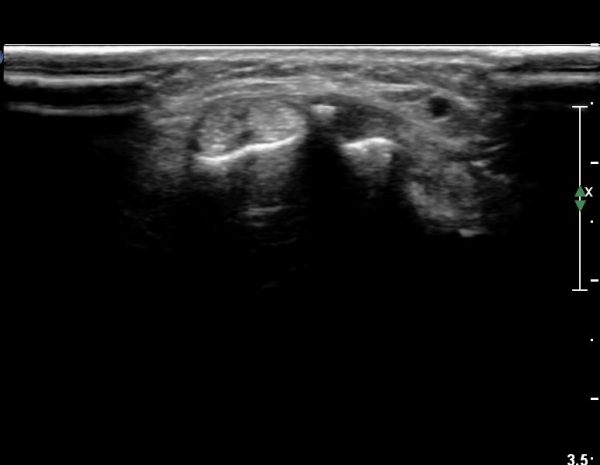

ŽÃËÀÚ¸¦ ¾à°£ ¸»´ÜÀ¸·Î À̵¿ÇÏ´Ï Àå, ´Ü¿äÃø¼ö±Ù½ÅÀü°Ç ºÎÁ¾°ú ÀÌ ½ÅÀü°Ç Ç¥ÃþÀ¸·Î ÁÖÇàÇÏ´Â

À幫Áö½ÅÀü°Ç(EPL)ÀÌ °üÂûµÈ´Ù(»çÁø 4, 5).